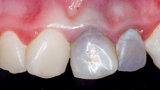

Indikační šíře MTA: Soubor kazuistik